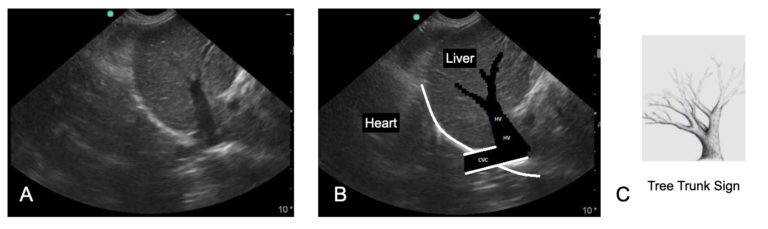

ECC and IM Blog- The Evolution and Another FASTVet Original – Characterization of the Caudal Vena Cava and Hepatic Veins

As you may know, my wife Stephanie Lisciandro, DVM, DACVIM (SAIM), was trained at The Animal Medical Center in the … Continue reading ECC and IM Blog- The Evolution and Another FASTVet Original – Characterization of the Caudal Vena Cava and Hepatic Veins